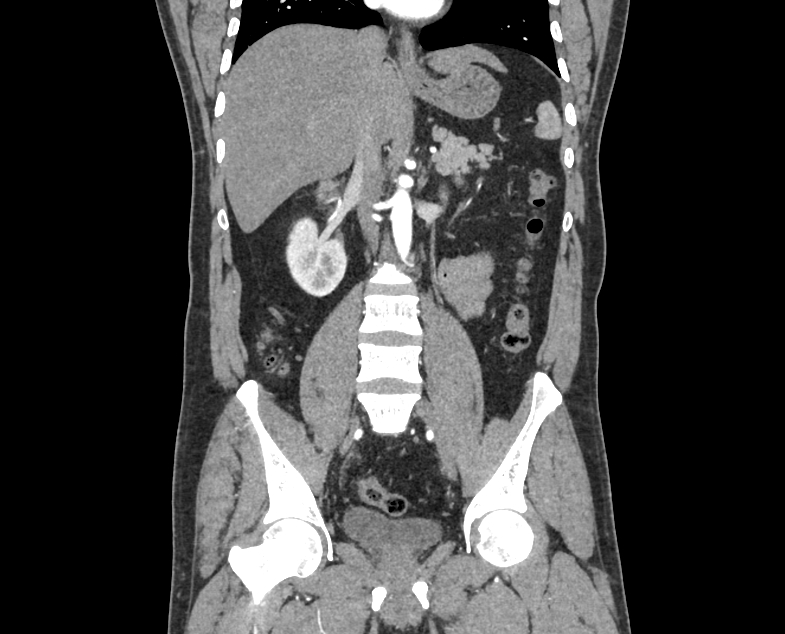

Figure 3 shows several samples from the dataset, with two scans of each dataset class.

Images of the dataset were selected from axial and coronal anatomical planes with and without contrast for the entire abdomen. The data format was DICOM and the images were converted to JPG format. The dataset originally contained 12,446 images, but we removed duplicate samples, reducing the total to 11,929 images. Table 2 shows the distribution of images into the four classes.